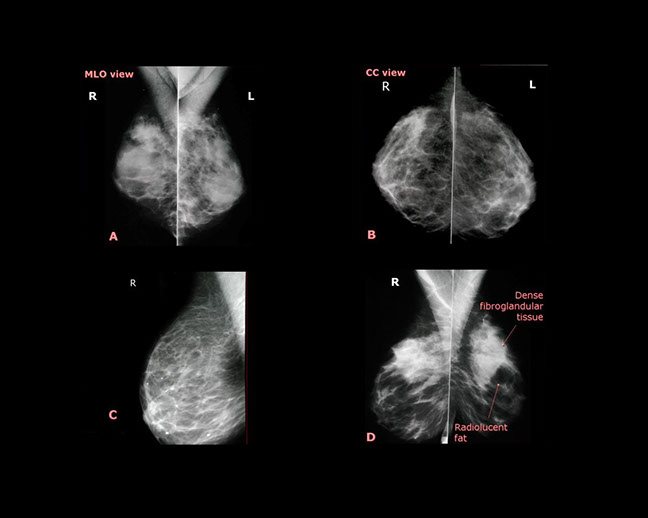

MAMMOGRAPHY

It became obvious that the training in interpreting Mammograms was occasionally deficient and with the assistance by Dr. Michael Moran, on staff in the Radiology Department a Two Day Mammography Course was created and given thirteen times in Centres in Australia and once in New Zealand.